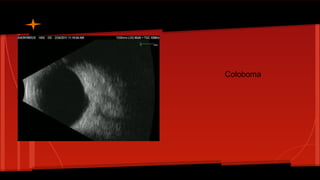

Coloboma